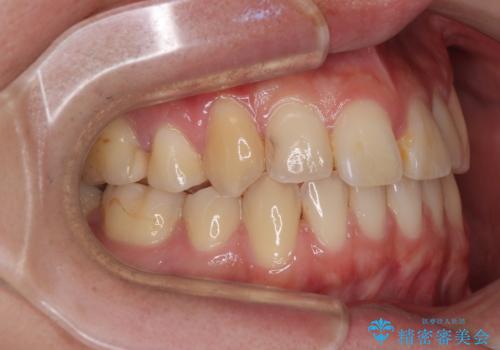

- 高校生の時に行った抜歯矯正の後戻りを気にして来院された患者様です。

インビザラインでの治療を希望されていて、デコボコの程度が中等度であり、安価なパッケージにて対応可能と判断されたため、インビザライン・モデレートを用いて矯正治療を行うこととしました。